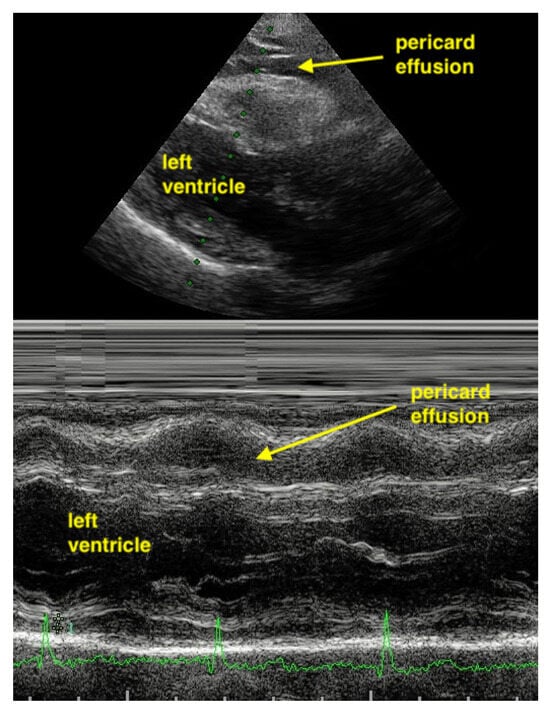

7.2.1. Pericardial Effusion

Pericardial effusions are best identified with a convex or sector probe in the subxiphoid or parasternal view. While it is important to simply note whether an effusion is present, sonographic and clinical (hypotension and tachycardia) evidence of cardiac tamponade should be sought. These include diastolic collapse of the right atrium free wall, followed by free wall collapse of the right ventricle as tamponade worsens. Both the apical and subcostal four-chamber views are ideal for this assessment. However, the subcostal window allows for a rapid transition to the proximal IVC view, which is dilated (>2 cm) and does not vary with respiration in cases of cardiac tamponade. Although many cases of medium and large pericardial effusions are obvious on ultrasound, there are notable exceptions. These include some hemorrhagic effusions which show significant coagulation, thus appearing echogenic on ultrasound, leading to frequent confusion with an epicardial fat pad or even a portion of the myocardial wall. Conversely, some epicardial fat pads may be confused with pericardial effusions, especially by novices. Differentiating between the two is easy by using anatomical knowledge. An epicardial fat pad does not extend enough inferiorly to be seen on a longitudinal IVC inlet view, while a pericardial effusion will in virtually all cases (Figure 7, Figure 8, Figure 9 and Figure 10).

Figure 7.

Pericardial effusion in parasternal long-axis view.

M-Mode can help to differentiate between pericardial effusion and fat. Pericardial effusion undergoes a fluctuation during heart movement and so shows a hypoechoic band which moves in thickness. In contrast, the hypoechoic band of fat does not change in thickness (Figure 11 and Figure 12).

Figure 11.

In the apical 4CV (Chambers almost not to see), in the apex is a broad hypoechoic band which has always the same size. 4CV = Four Chamber view.

Figure 12.

In the parasternal long-axis view, the hypoechoic band of the pericardial effusion varying in size during heart contraction (undulating).